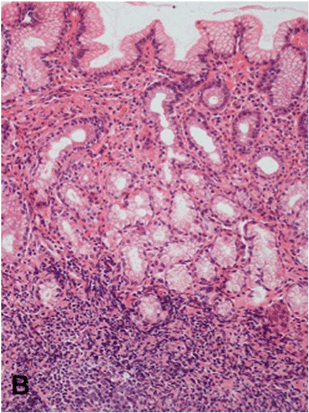

| Figure 2B: Gastric antral mucosa-H pylori-induced chronic gastritis, with marked inflammatory infiltrate in the lamina propria and presence of a lymphoid follicle (arrow). The glands are preserved (arrowheads) although separated by the infiltrate. (H&E, x200). |